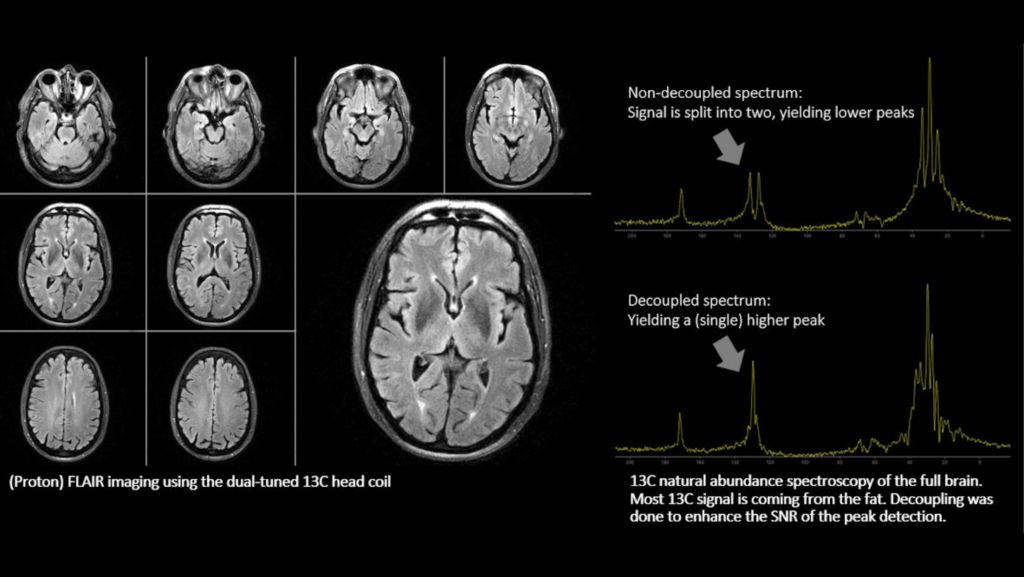

Brain exams, without switching coils

In addition to a seamless user interface, the dual tuned head coils from <b><i><i>RAPID biomedical</i></i></b> enable brain exams, including acquisition of proton and other nuclei, without switching coils. This allows you to schedule your multi-nuclei studies as part of your clinical exam time slots. A full brain study, including both proton (1H) and sodium (23Na) imaging can be completed in 30 minutes¹, all organized in one ExamCard using the same dual tuned head coil. A sodium (23Na) brain exam can be completed in less than 15 minutes².

The dual tuned head coil from RAPID Biomedical allow you to perform brain exams, including acquisition of proton and other nuclei (31P, 13C, 23Na), without switching coils, in routine scan times. A full brain study, including both proton (1H) and sodium (23Na) imaging can be completed in 30 minutes, all organized in one ExamCard, using the same dual tuned head coil. A Sodium (23Na) brain scan can be completed in less than 15 minutes. Workflow does not differ from proton imaging. Multi-nuclei imaging and spectroscopy can be run and reconstructed directly from the standard user interface. The ExamCard interface immediately recognizes the dual tuned head coil. And the nucleus is just a scan parameter like any other sequence parameter. Viewing of multi-nuclei images and spectra, as well as sending data to PACS, is fully integrated. Combined with our multi-nuclei specialist package, the dual tuned head coil allows to explore new imaging pathways by integrating multi-nuclei studies in your day-to-day workflow.

4 Compared to non-decoupled spectroscopy results